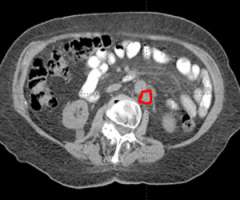

Stereotactic Body Radiation Therapy (SBRT) is a treatment procedure similar to central nervous system (CNS) stereotactic radiosurgery, except that it deals with tumors outside of the CNS. A stereotactic radiation treatment for the body means that a specially designed coordinate-system is used for the exact localization of the tumors in the body (Figure 1) in order to treat it with limited but highly precise treatment fields. SBRT involves the delivery of a single high dose radiation treatment or a few fractionated radiation treatments (usually up to 5 treatments). A high potent biological dose of radiation is delivered to the tumor, improving the cure rates for the tumor, in a manner previously not achievable by standard conventional radiation therapy (Figure 2).